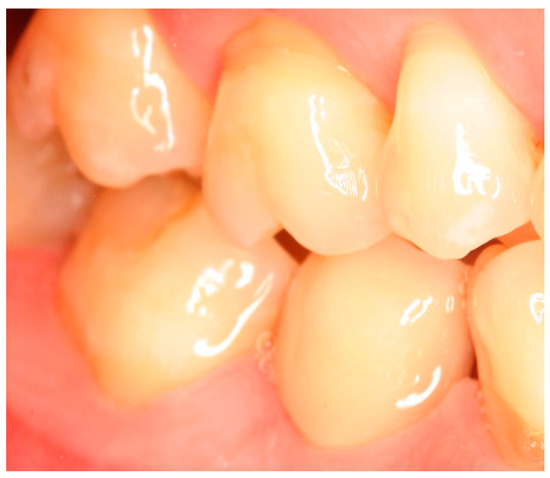

Situation after crown cementation. Lateral view.

Clinical situation at the 1-year follow-up. Lateral view.

Clinical situation at the 3-year follow-up. Lateral view.

Clinical situation at the 5-year follow-up. Lateral view.